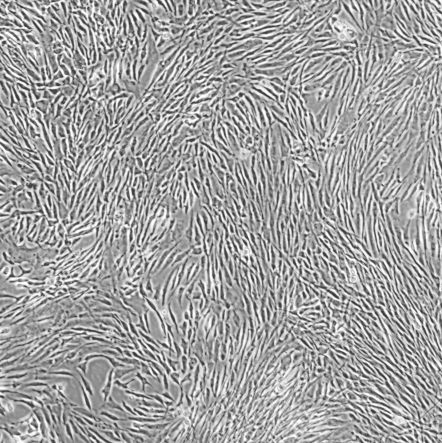

G-292, clone A141B1_人骨肉瘤细胞

细胞名称:G-292, clone A141B1 _ 人骨肉瘤细胞

种属来源: 人

性别年龄:女性

种属来源: 骨

生长特性: 贴壁生长

细胞形态: 成纤维细胞

培养条件: McCoy's 5a Medium Modified+10% fetal bovine serum,37 ℃, 5% CO2